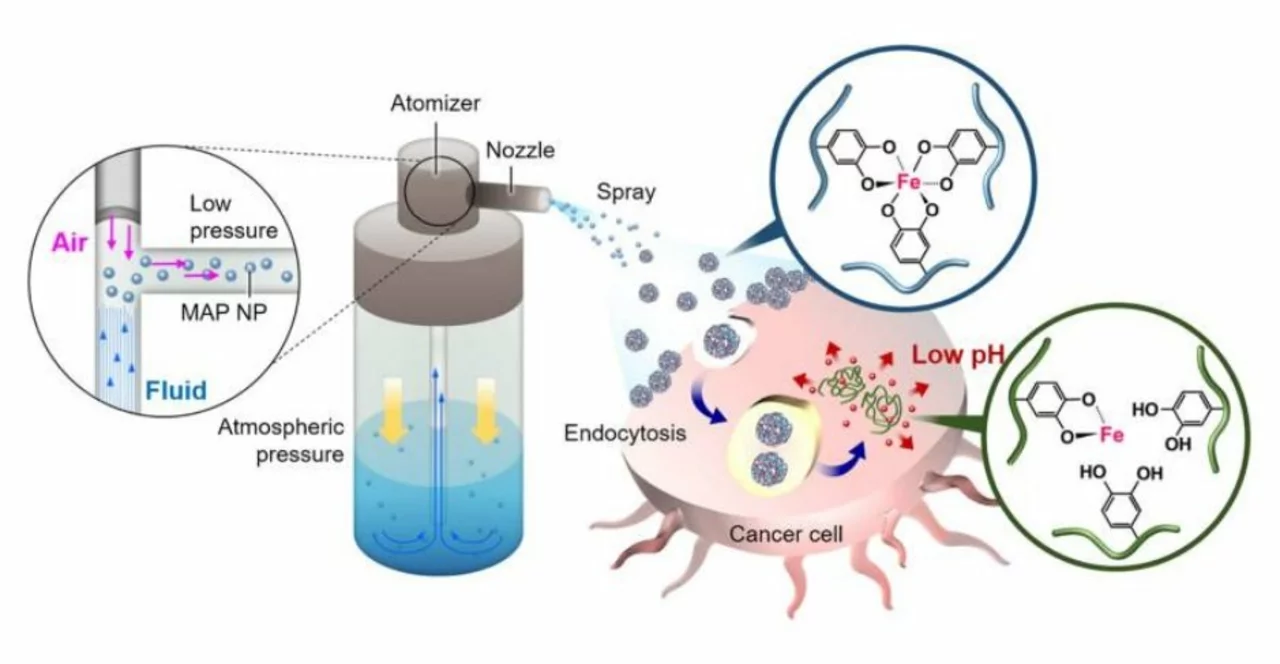

Bemzocaine and Its Role in Cancer Treatment

In my latest blog post, I delve into the fascinating world of Bemzocaine and its role in cancer treatment. Bemzocaine, a lesser-known compound, has recently gained attention for its potential in targeting cancer cells and improving patient outcomes. Researchers are focusing on understanding how this compound interacts with cancer cells, helping to reduce the side effects of chemotherapy while increasing its effectiveness. I also discuss the ongoing clinical trials and the future possibilities of Bemzocaine in revolutionizing the way we approach cancer treatment. Don't miss out on this exciting and informative read!